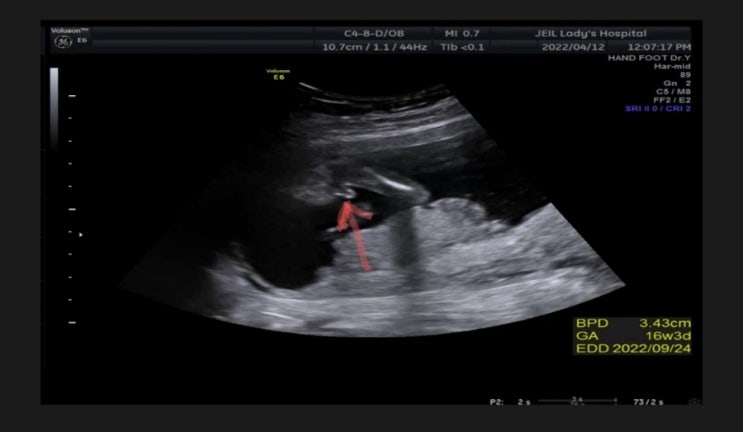

임신16주,17주,18주/ 성별확인, 태동

16주 성별확인 의사선생님이 초음파를 보면서 "뭐가 있네요" 순간 무슨 말인지 눈치 못 채고 &qu...